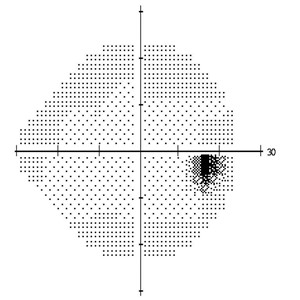

(图左:视力正常人士的视野;图右:晚期青光眼患者的视野)